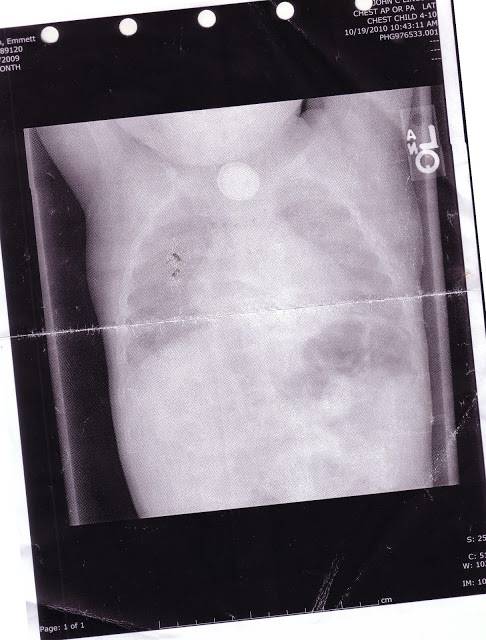

Qui una lastra ha mostrato che il litio perso dalla batteria stava danneggiando l’esofago e il tratto digestivo del bimbo.